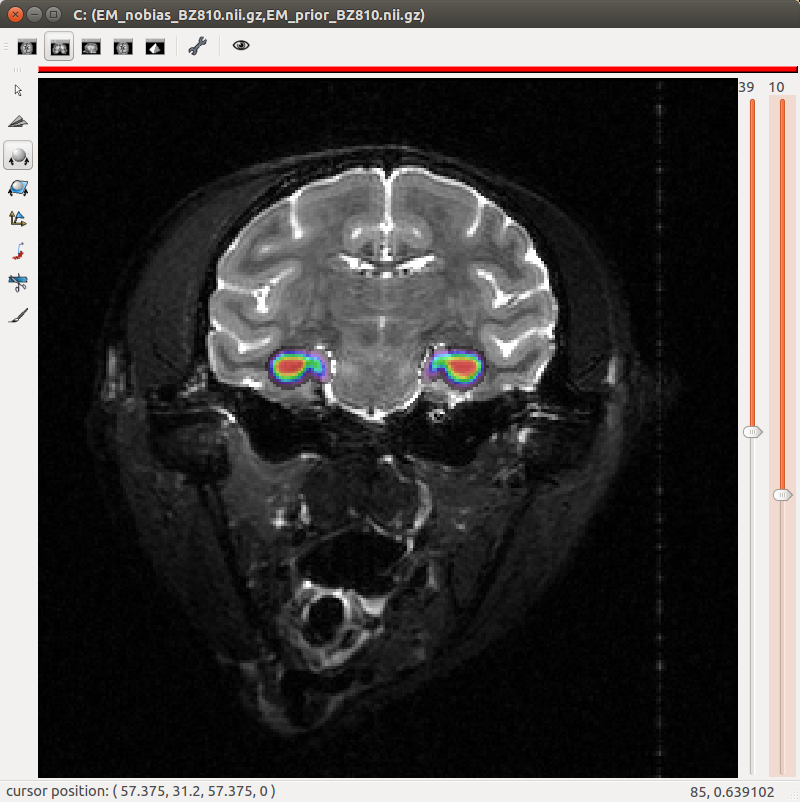

Figure 5. "Eye" visualization of the prior probabilities for classes "isocortex", "white matter" and "dorsal pallium".